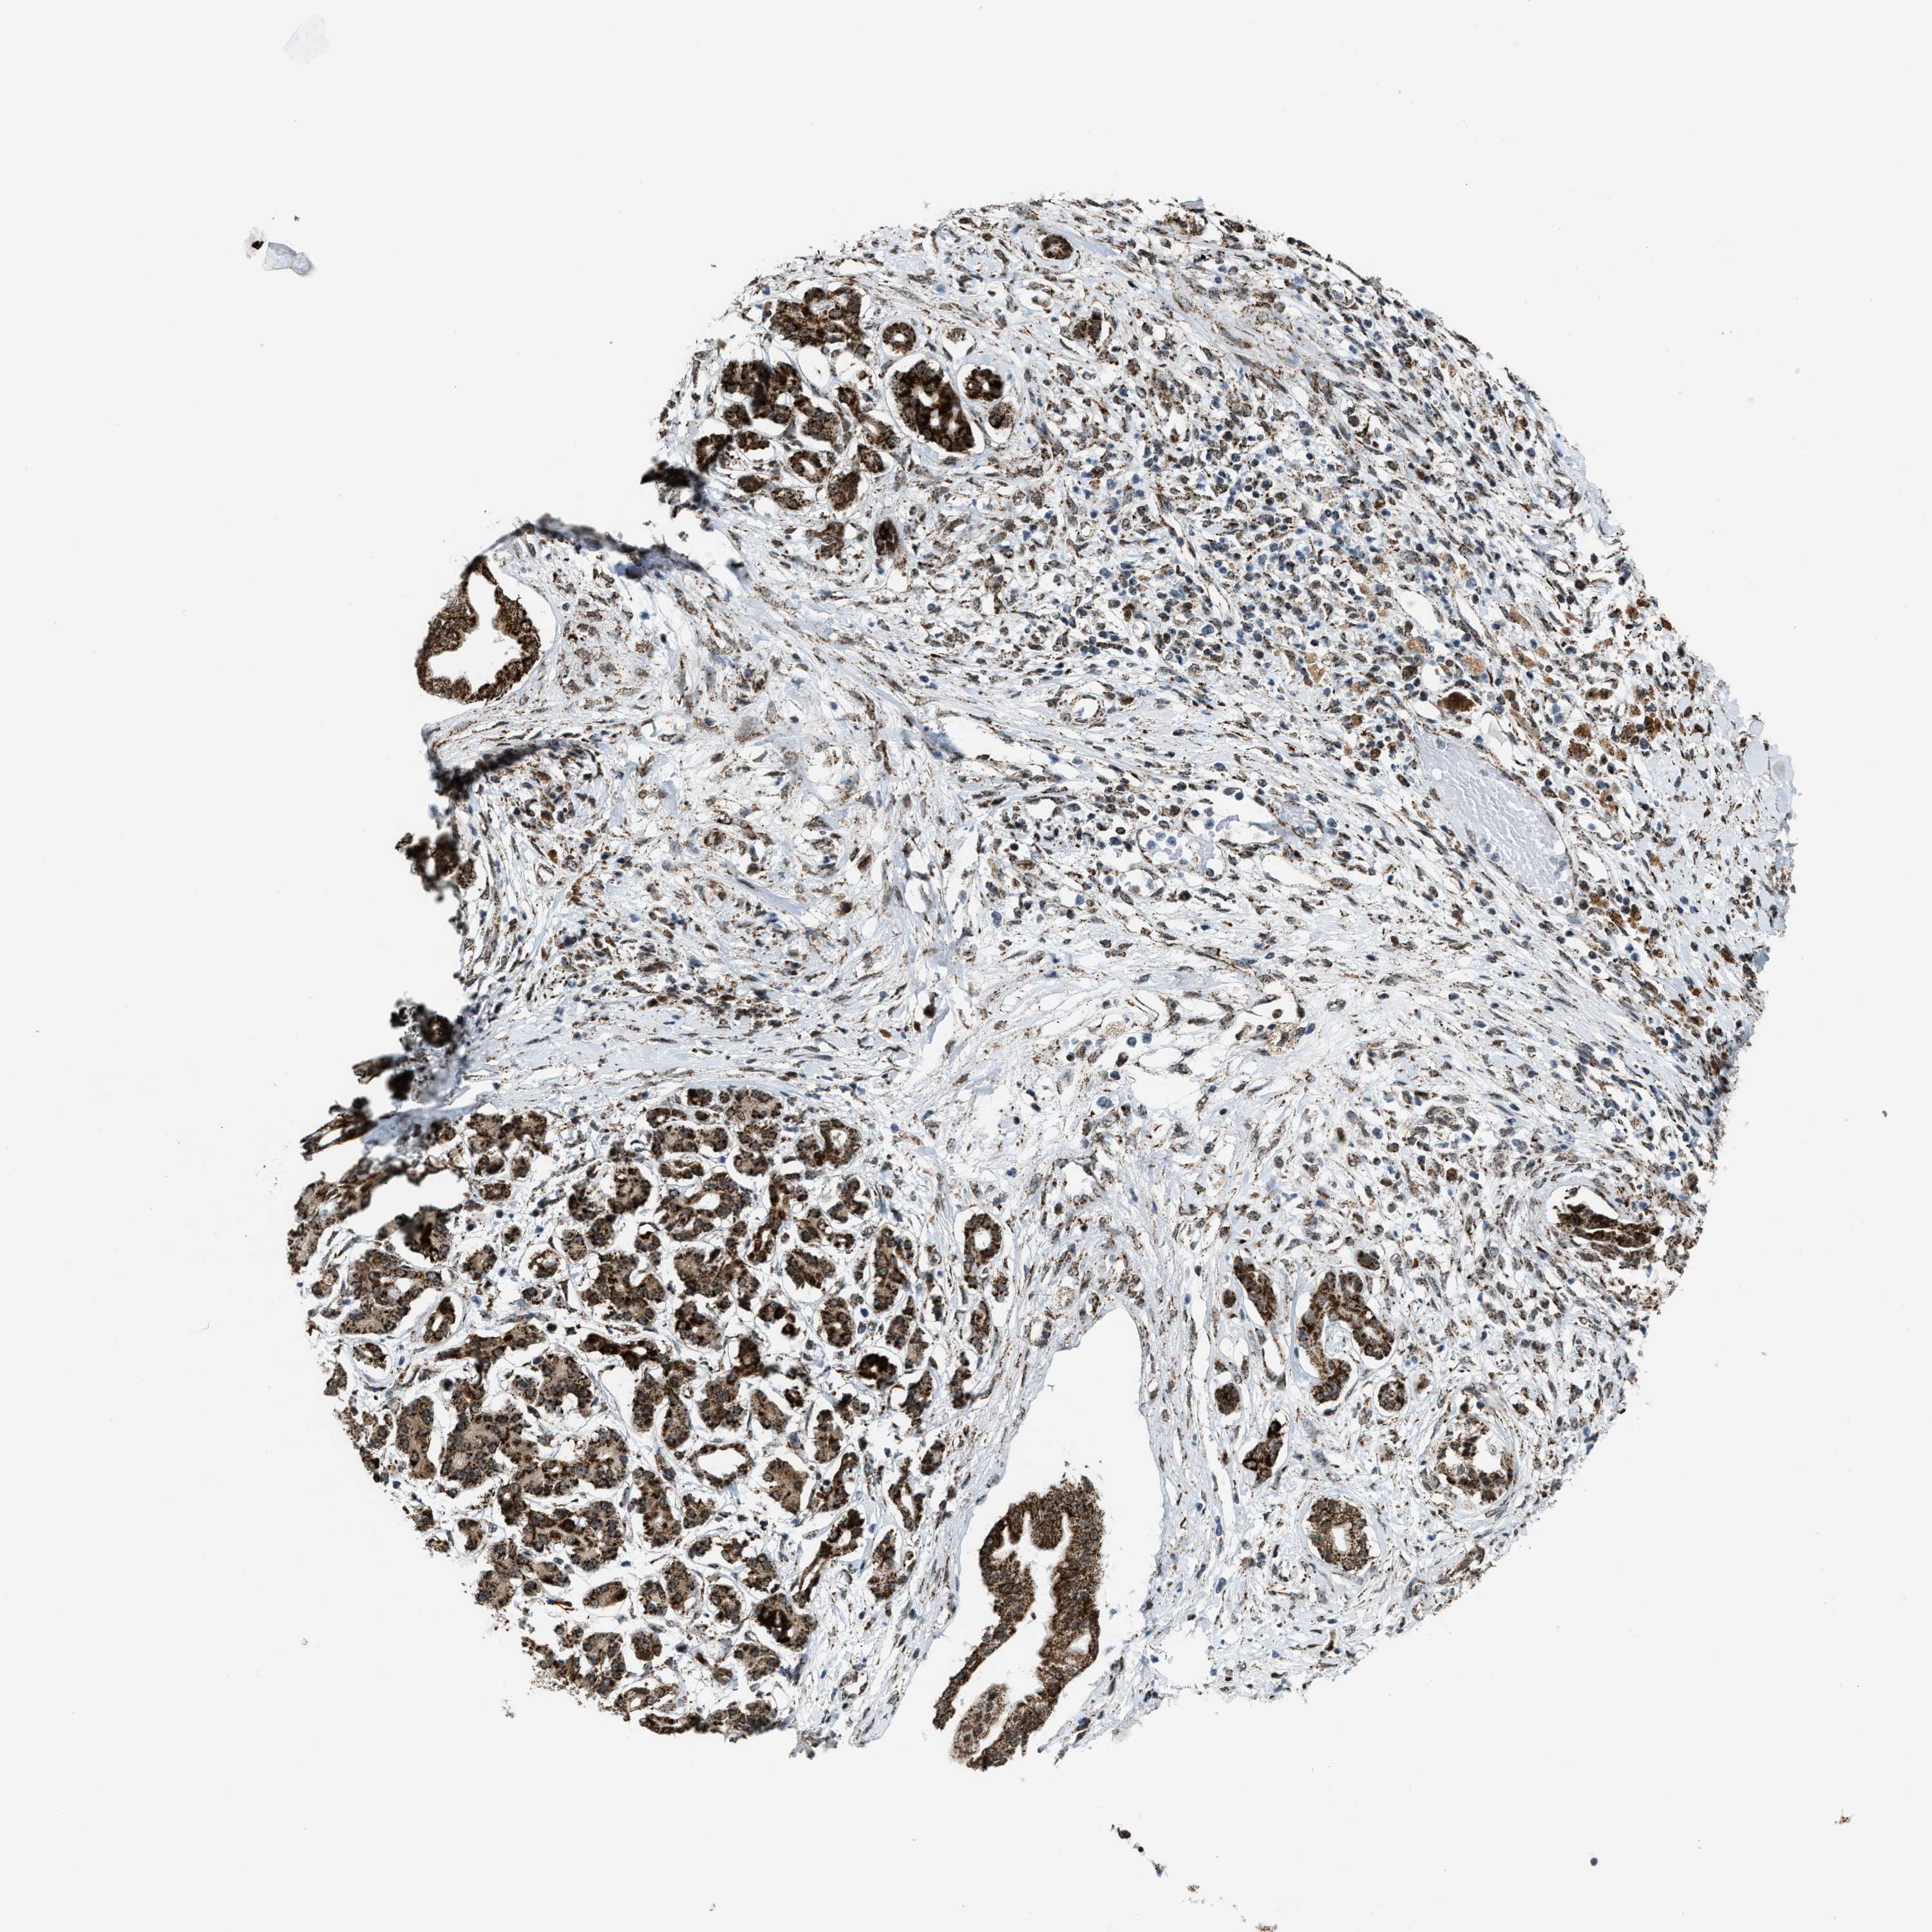

PANCREATIC CANCER - Protein expressioni

A mouse-over function shows sample information and annotation data. Click on an image to view it in a full screen mode. Samples can be filtered based on level of antibody staining by selecting one or several of the following categories: high, medium, low and not detected. The assay and annotation is described here.

Note that samples used for immunohistochemistry by the Human Protein Atlas do not correspond to samples in the TCGA dataset.

Antibody stainingi

Antibody staining in the annotated cell types in the current human tissue is reported as not detected, low, medium, or high, based on conventional immunohistochemistry profiling in selected tissues. This score is based on the combination of the staining intensity and fraction of stained cells.

Each image is clickable and will lead to virtual microscopy that enables deeper exploration of all samples and also displays staining intensity scores, fraction scores and subcellular localization as well as patient and tissue information for each sample.

Antibody HPA019522

Antibody HPA021002

Staining

High

Medium

Low

Not detected

Intensity

Strong

Moderate

Weak

Negative

Quantity

>75%

75%-25%

<25%

None

Location

Nuclear

Cytoplasmic/membranous

Cytoplasmic/membranous,nuclear

Adenocarcinoma, NOS